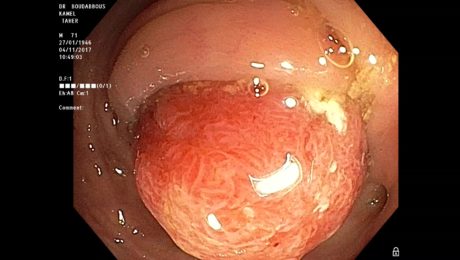

polypectomie avec mise en place d’une endoloop